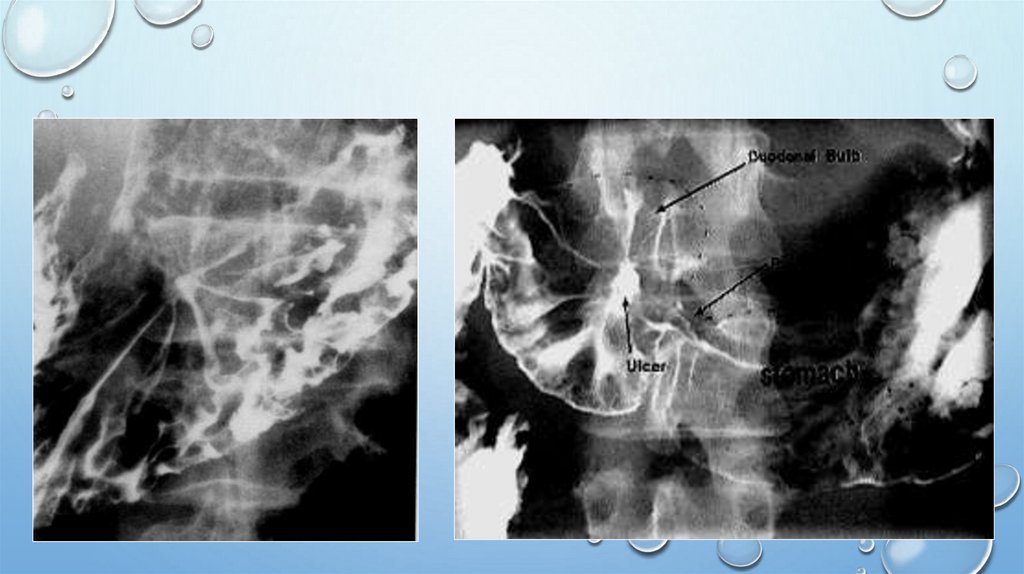

Язва желудка

Проявление в виде ниши на рельефе =депо бария

Депо бария. Воспалительный

вал вокруг язвы. Конвергенция

складок к язве.

Ниша на рельефе с

конвергенцией

складок к язве. Двойное

контрастирование

(пневморельеф).

Больной

лежит на животе.

51. Локальное расширение и изменения рельефа желудка - Язвенная болезнь.